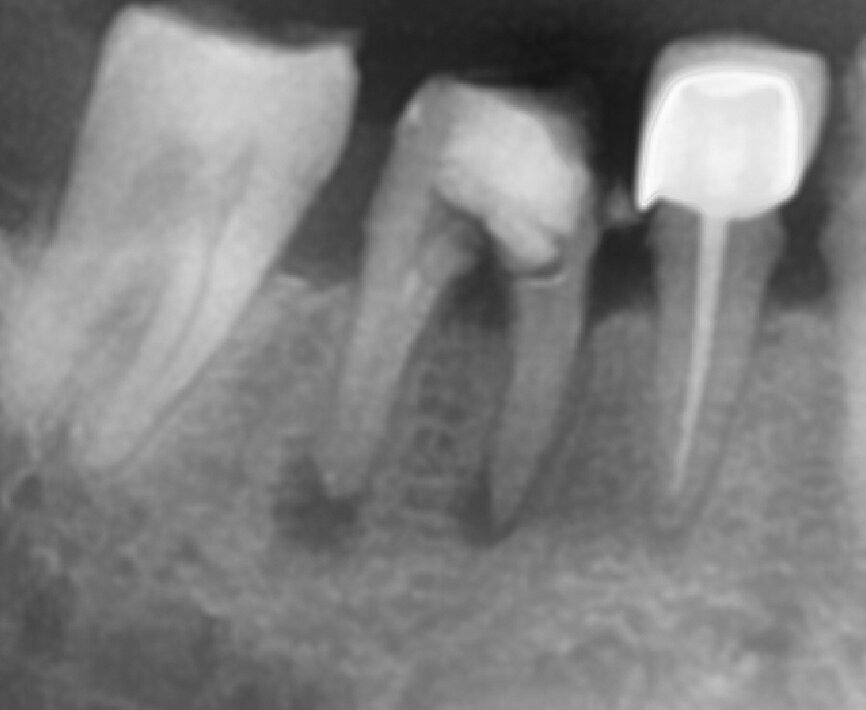

Fig.1b: Pre-op radiograph taken by the author in relation to tooth #46 (January 2019).

When I had a close look at the preoperative radiograph from the referring dentist (Fig. 1a), I observed that there was insufficient obturation of the mesial canals and almost no obturation of the distal canal. Both roots displayed periapical radiolucency. The clinical examination revealed a Grade I mobility, and the tooth was tender to percussion. The periodontal examination ruled out any pockets and loss of attachment. We took an intra-oral periapical radiograph (Fig. 1b), from which we observed the loss of coronal structure and a large radiolucent area over the furcation area and the periapical area of both the mesial and the distal roots. A CBCT scan of tooth #46 was advised to check for any details that may have been missed in the intra-oral periapical radiograph (Figs. 2a–g). From the CBCT scan, it could be observed that there was inadequate obturation of the distal canal on the horizontal plane, no obturation beyond the middle third in the mesial canals and a breach of the floor of the pulp chamber. The questionable prognosis was explainedto the patient, and written consent was obtained.